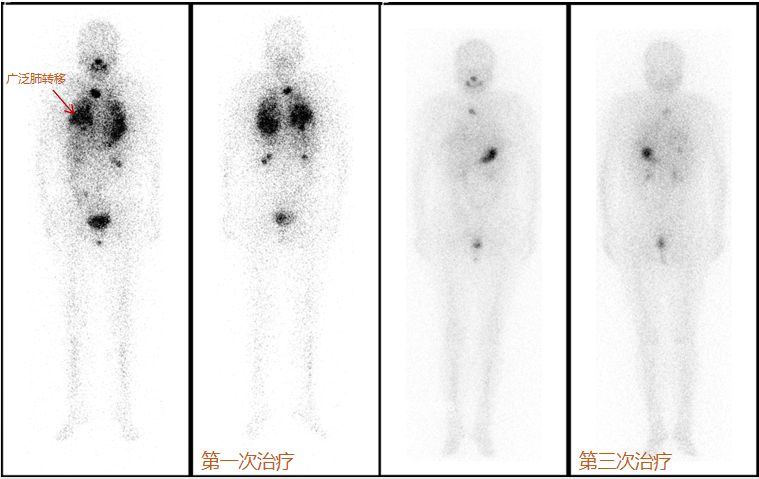

肺转移:甲状腺癌发生肺转移,根据转移灶的大小、多少及分布情况不同有多种表现。多发小结节肺转移癌碘-131治疗效果最好,患者经过多次治疗能达到临床治愈目的。比如下面这个甲状腺弥漫性肺转移的病人经过3次碘-131治疗,肺部病灶几近消失。

甲状腺癌肺转移

多发大结节性肺转移碘-131治疗效果不如多发小结节,但大多数患者经过治疗后结节可以缩小,部分甚至消失,临床病情明显缓解。因此,肺转移患者只要病灶能摄取碘-131,就是治疗的指征。